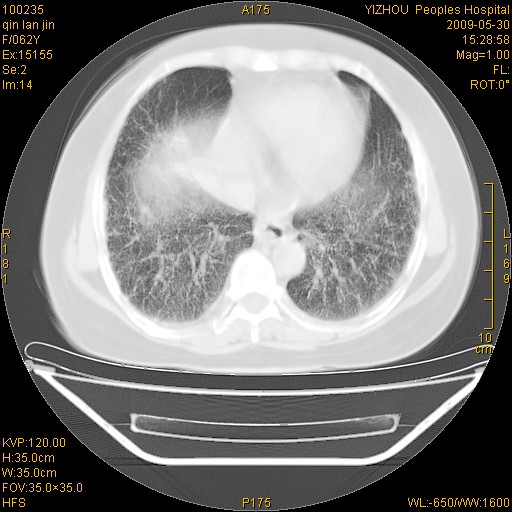

标题: CT20268:肺泡癌?间质性肺炎? [打印本页]

标题: CT20268:肺泡癌?间质性肺炎?

女,62岁,近二年经常咳嗽,近二个月,消瘦、乏力。

两肺弥漫性间质性病变(间质性肺炎伴肺间质纤维化?)。

间质性肺炎伴肺间质纤维化。

纵隔淋巴结大,须排外癌性淋巴管炎